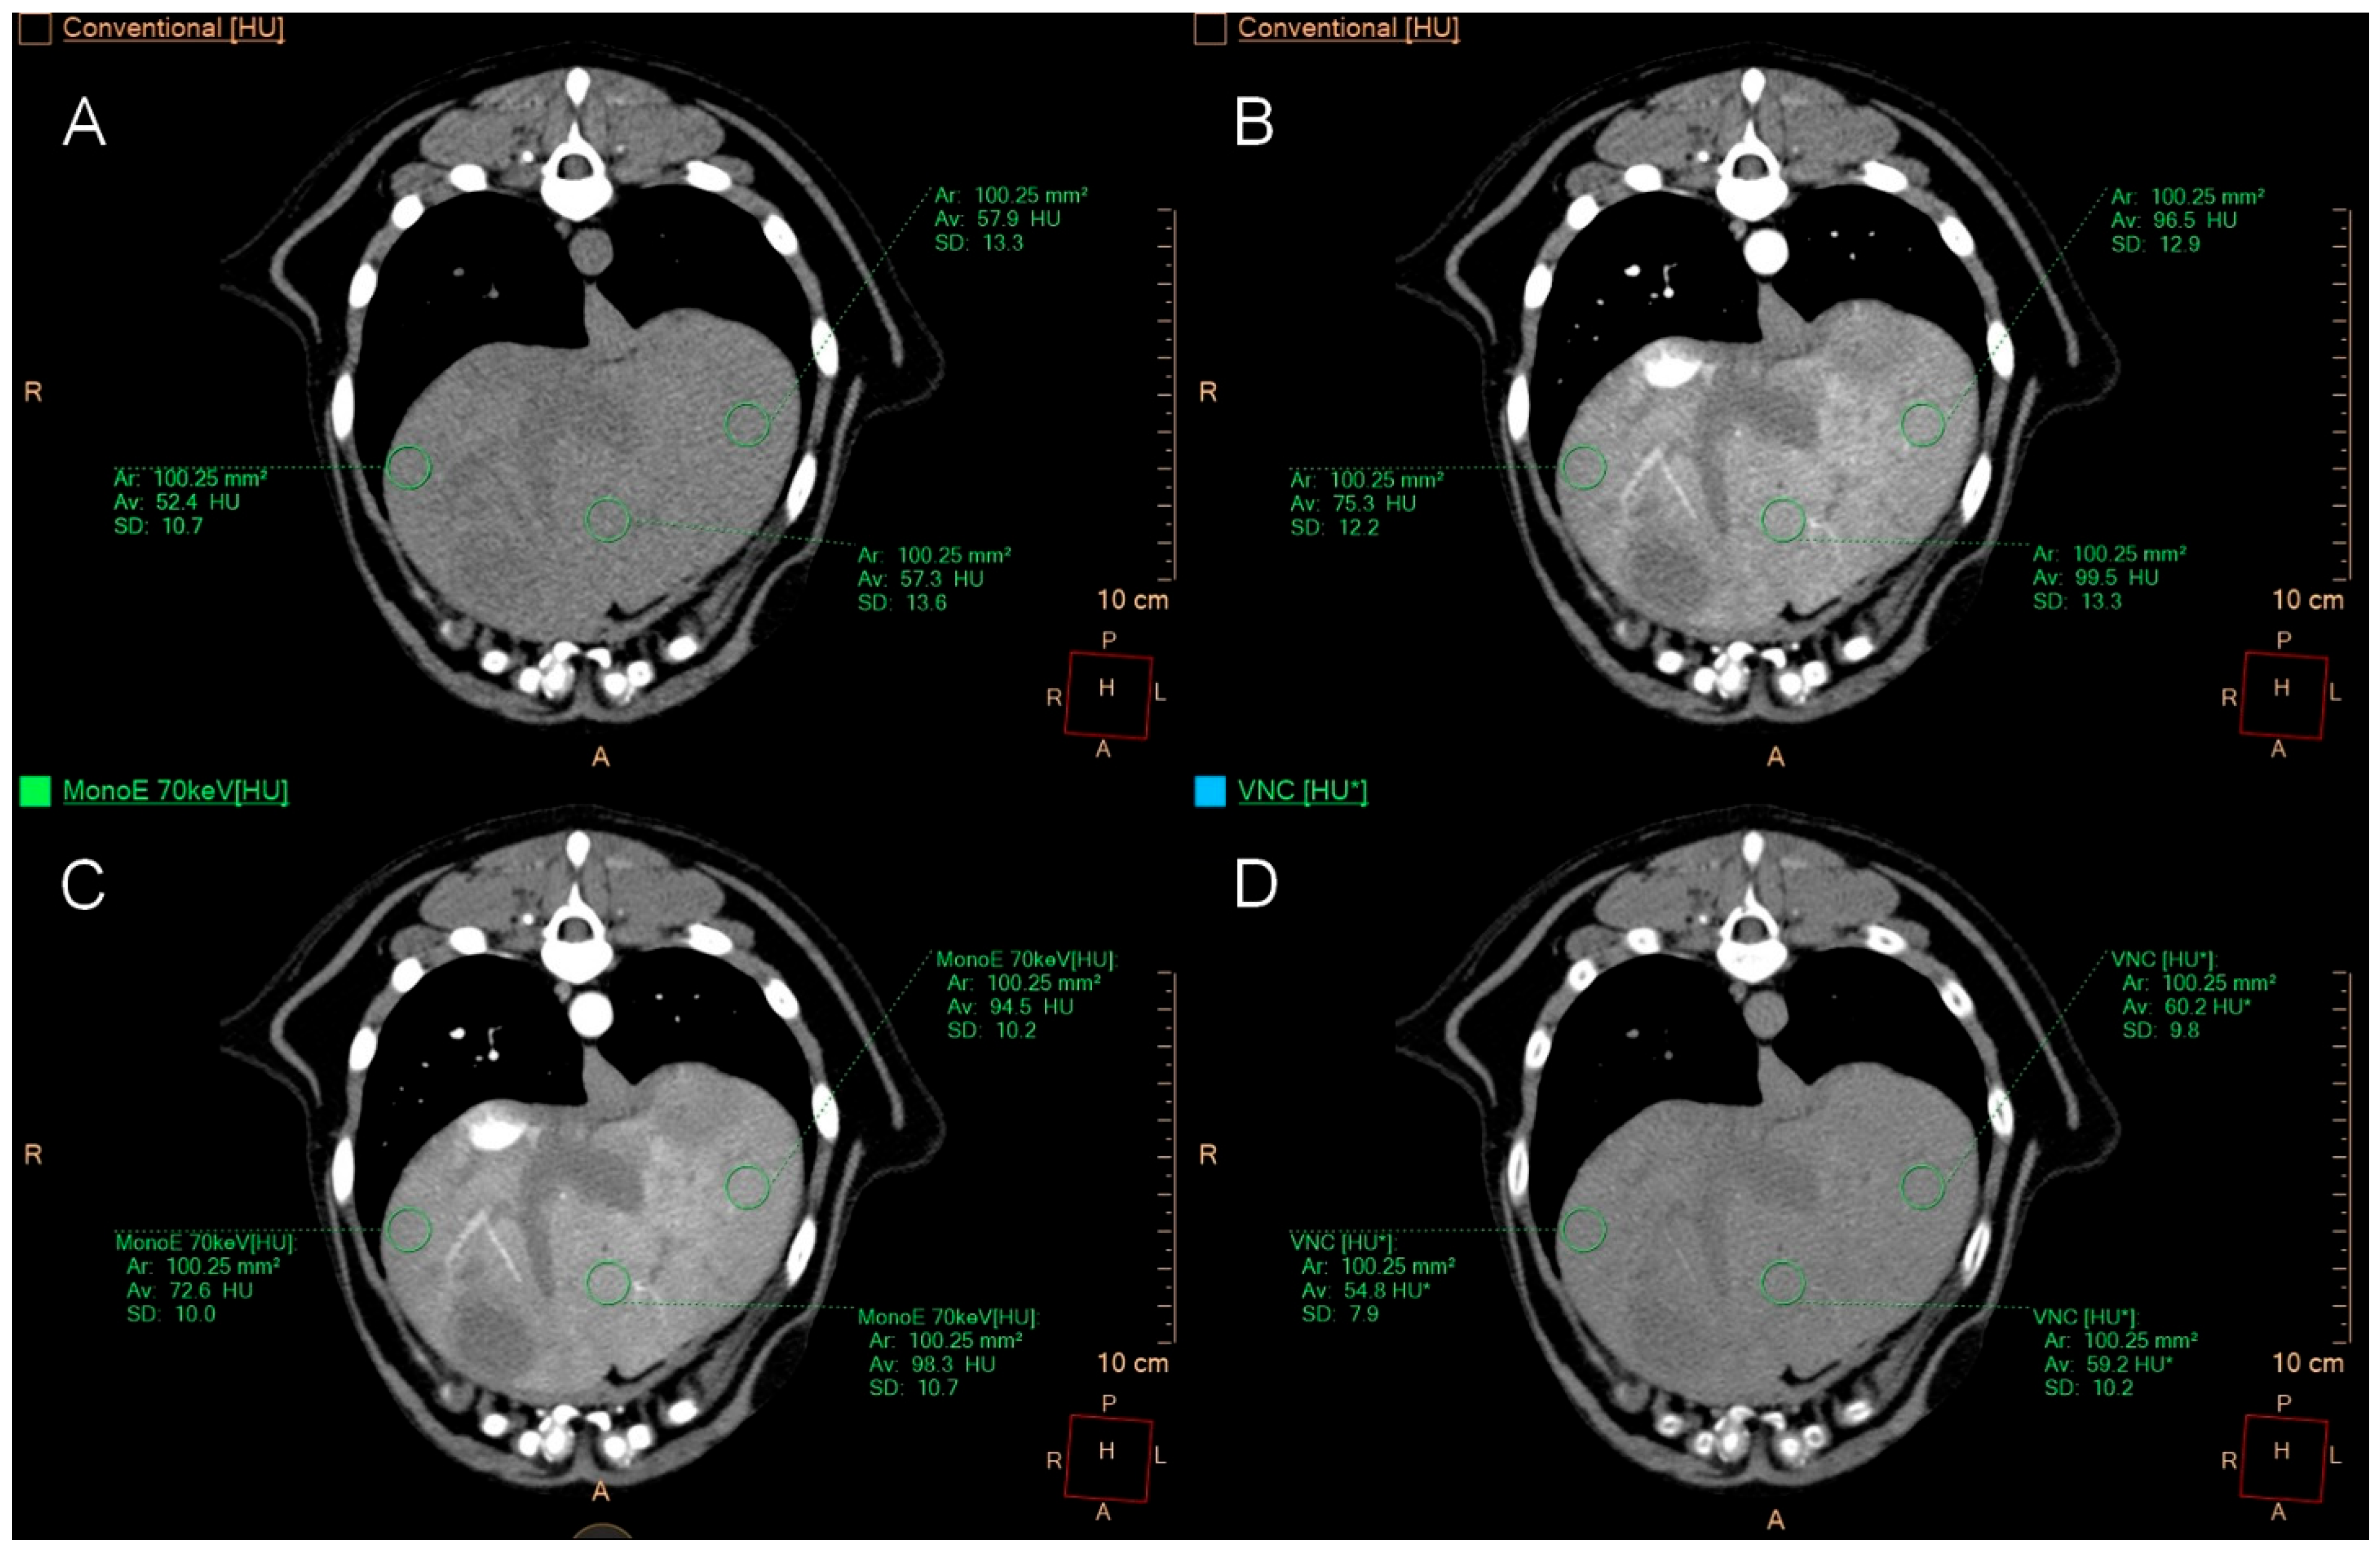

2.4. Quantitative Image Analysis

3.4. Quantitative Image Analysis